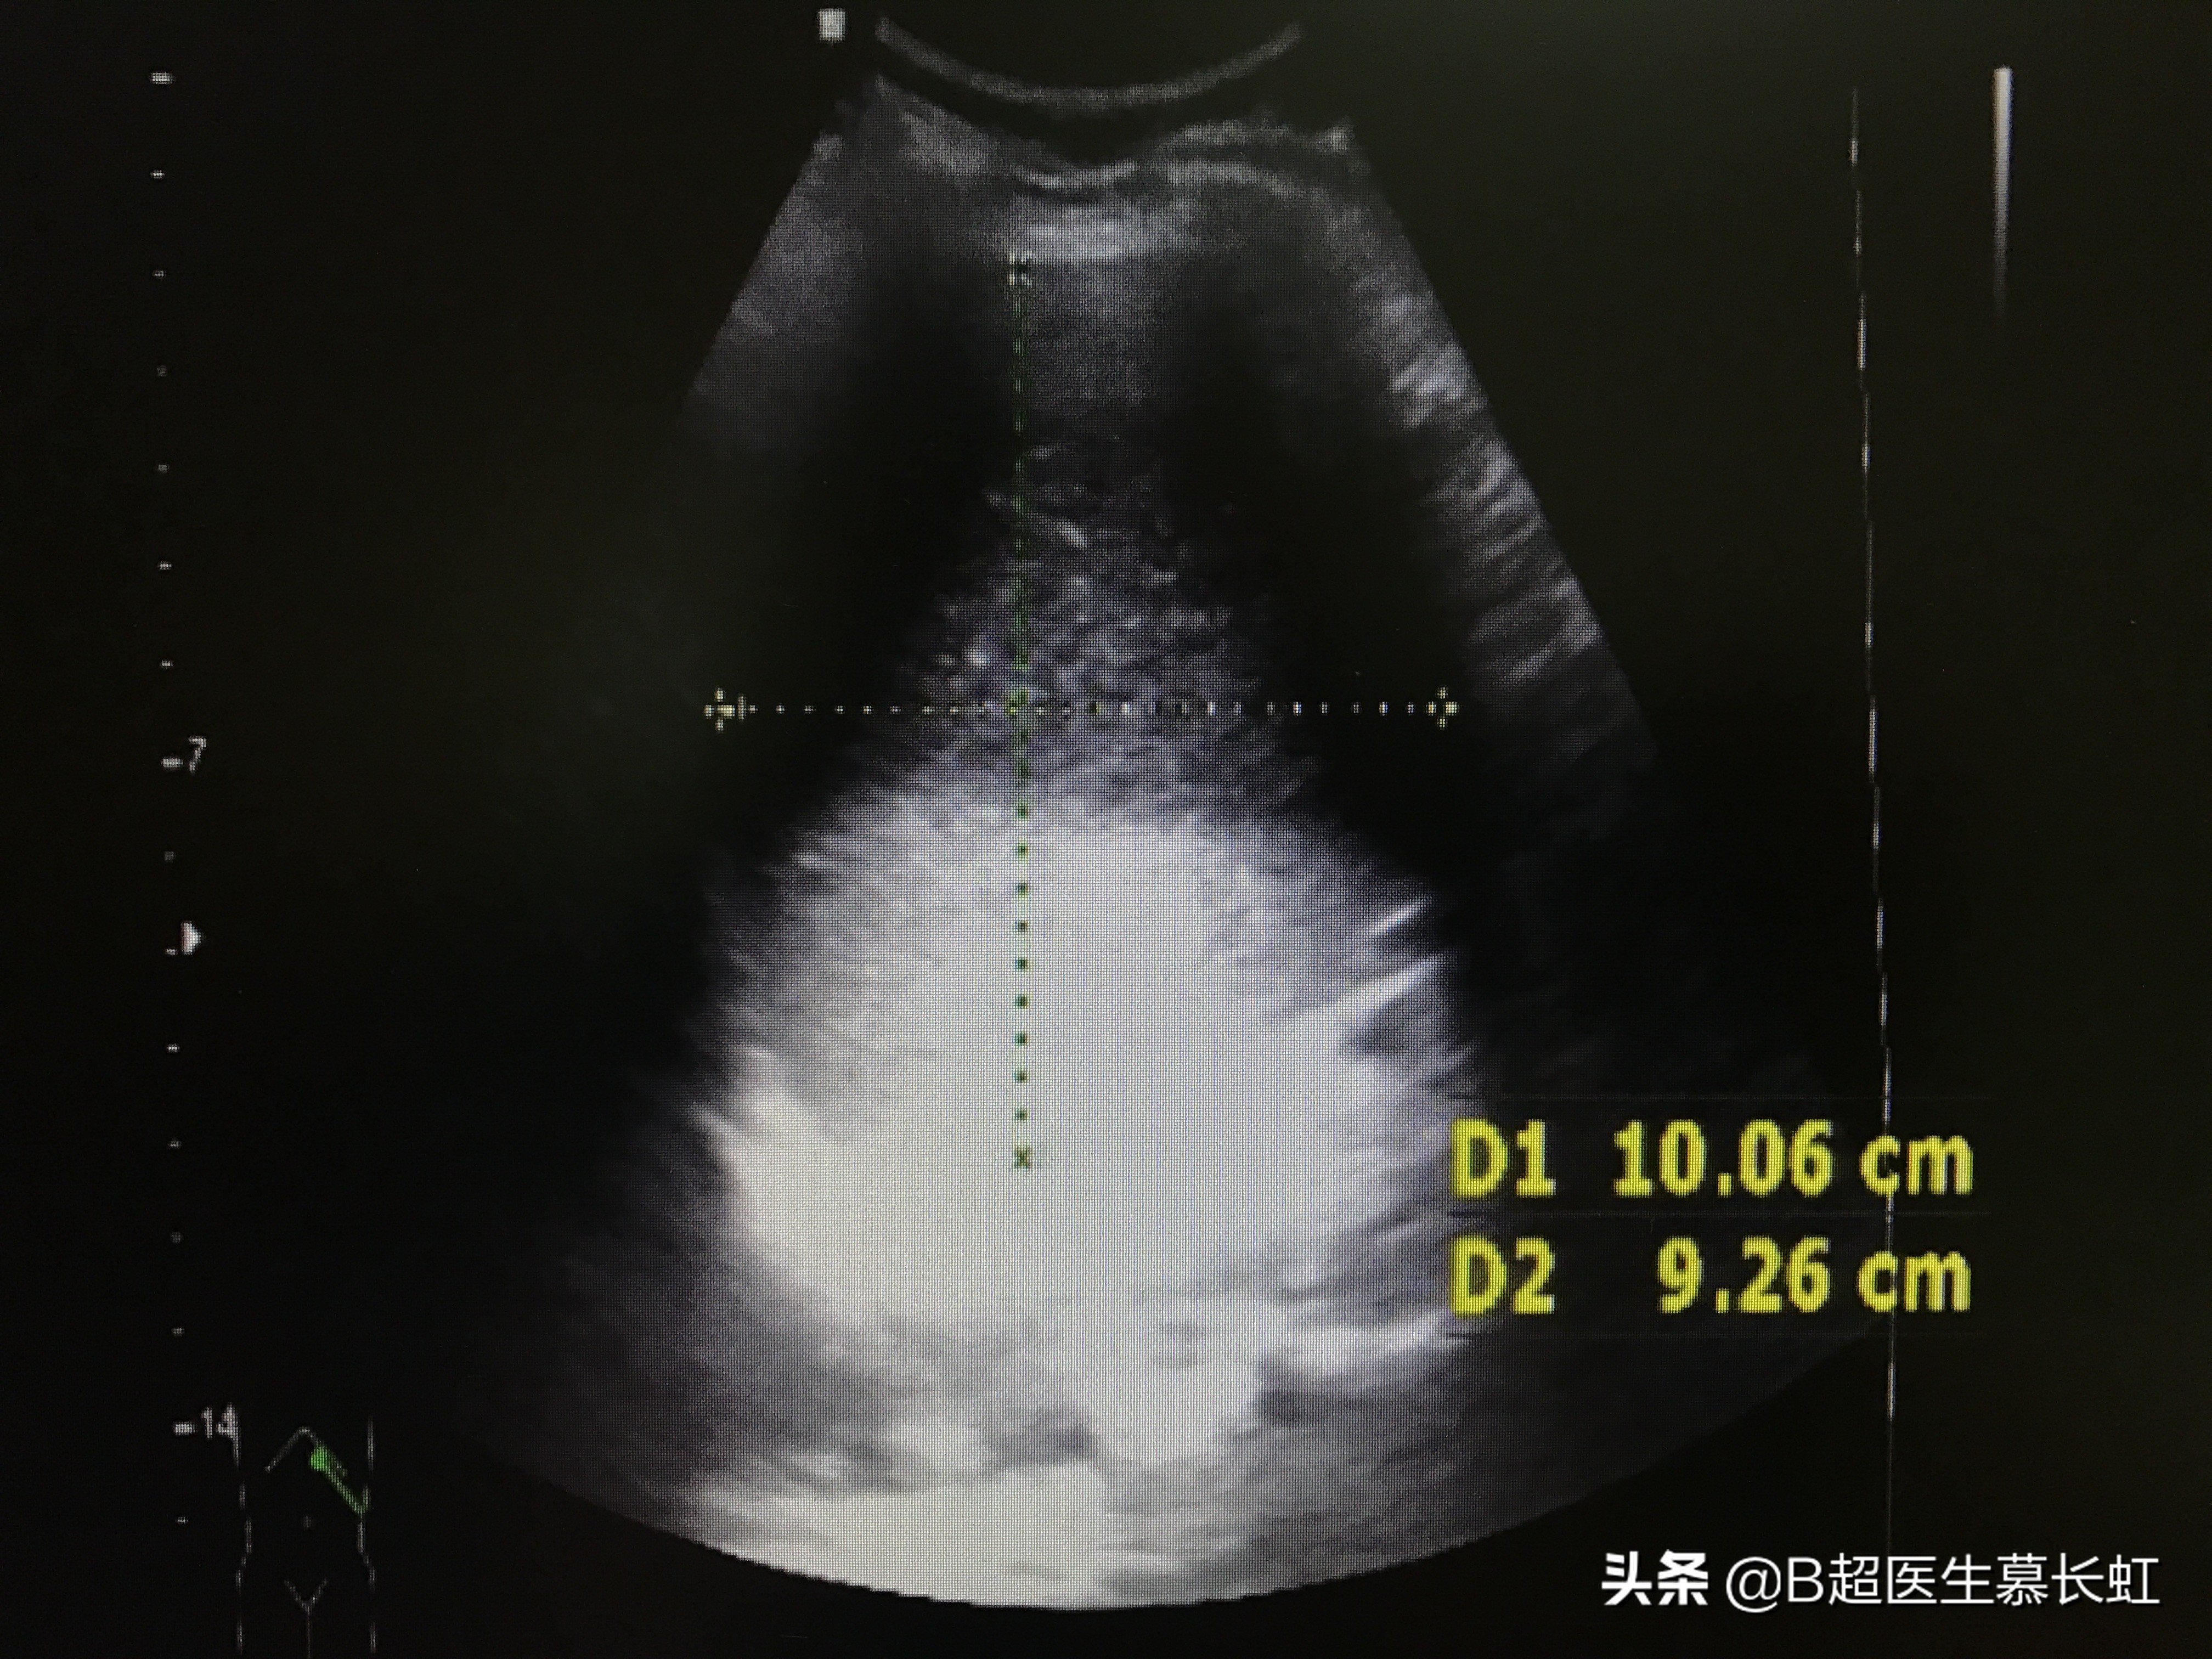

超声检查腹部实质脏器,肝胆脾胰肾都没问题,但是发现胃部扩张,胃内有大量混杂着粥样物的浑浊液体。可是阿姨已经三天没怎么吃饭喝水了呀,那胃内这么多粥样液体是怎么回事呢?

胃内充满大量粥样浑浊液体

想着阿姨已经几天没吃东西没喝水了,但是胃内又有这么多东西,应该是下消化道有梗阻了吧。

然后腹部全面扫查,发现肠管的确有异常。

就是围绕着腹部,从右下腹、右侧腹部、右上腹部、一直到左上腹部,肠管都是扩张着的,里面有杂乱的浑浊液体。